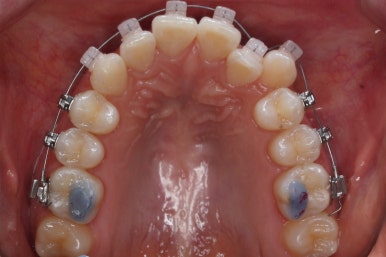

부산부정교합 키다리아저씨치과에서 장치를 처음 부착한 모습입니다.

많이 삐뚤어진 부위는 철사가 굽이굽이 지나가는 것을 볼 수 있습니다. 이 철사가 점점 직선으로 가지런해지면서 치아가 바르게 가지런해집니다.

부산부정교합 키다리아저씨치과에서 처음 장치를 부착한 모습입니다.